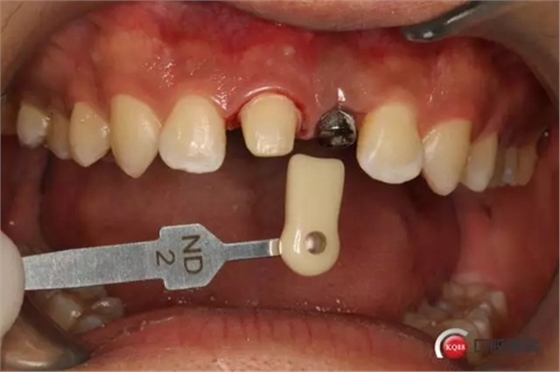

種植后修復,我們要把握每一個細節(jié),比色,轉(zhuǎn)移桿的就位,我們必須把臨床做好,技工師傅才會給我們做出好的修復體,減少一些不必要的失誤,首先術前的檢查是必要一步 ,再是器械的準備使我們臨床操作有條不紊,術前拍照,o-bite取咬合記錄,消毒修復術區(qū),旋出愈合基臺,生理鹽水沖洗袖口,拍照袖口,安放合適轉(zhuǎn)移桿,拍X線見轉(zhuǎn)移桿就為良好,硅橡膠取模,術后旋回愈合基臺,拍照比色。

藻酸鹽對頜取模,超硬石膏灌注。發(fā)加工廠,與技工溝通注意事項,等修復體做好后,檢查模型。是否就位,是否密合,預約患者復診戴牙,消毒修復區(qū),旋出愈合基臺,定位器指導安放修復基臺,試戴冠,調(diào)磨鄰接及 咬合至合適,拋光,患者滿意,加力扳手加力至30N,拍X片見就位良好,特芙蓉及暫封膏封中央螺絲孔,聚羧酸鋅粘固劑粘固,或是樹脂水門汀粘固,清理多余粘結(jié)劑,光固化樹脂封螺絲孔,拋光。術后注意隨訪。